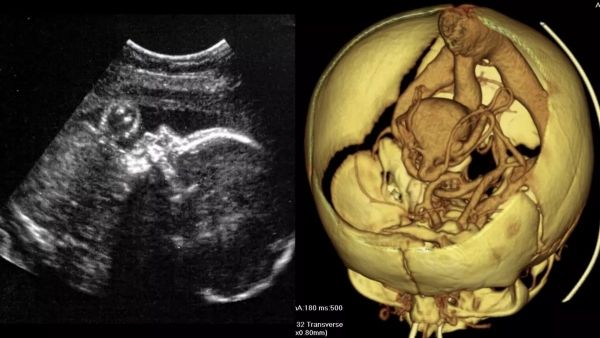

الأولى بالعالم.. أطباء يجرون جراحة لدماغ جنين في رحم أمه